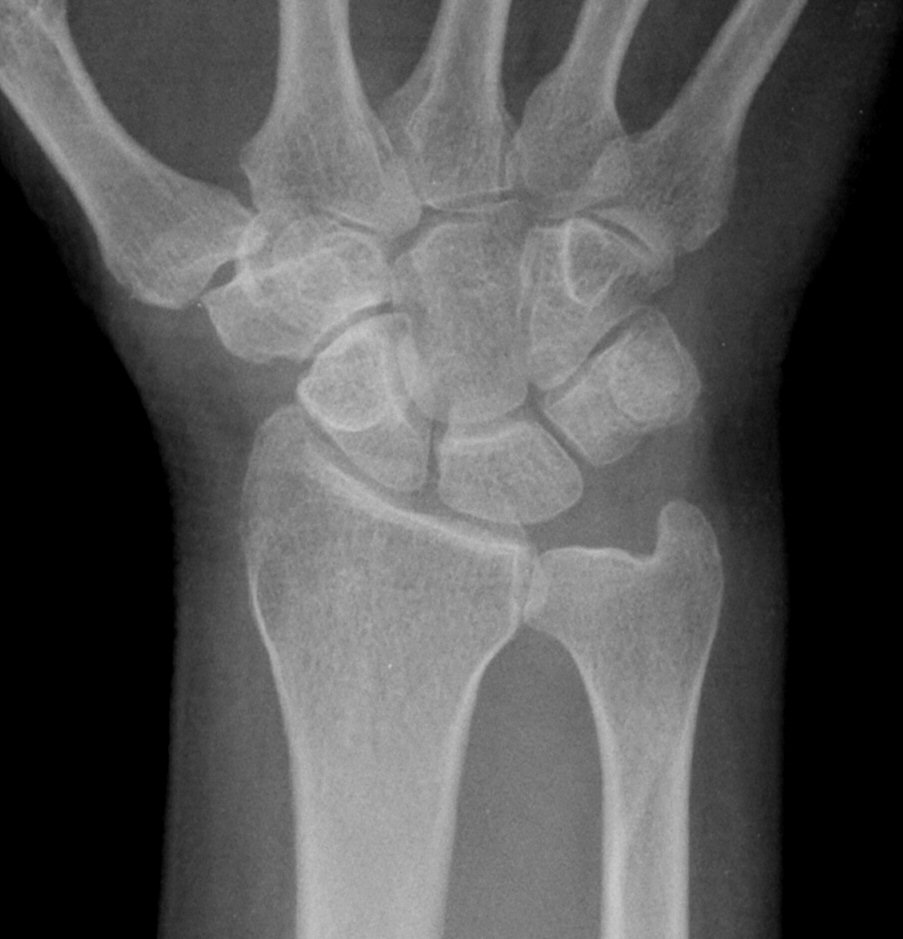

´Ü¼ø¹æ»ç¼±°Ë»ç

ƯÀÌ ¼Ò°ß ¾øÀ½(÷ºÎ ÆÄÀÏ)